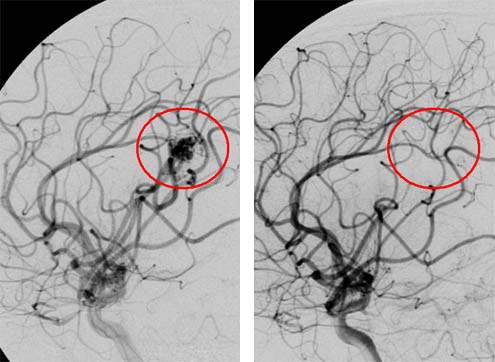

Dieses Behandlungsbeispiel zeigt eine zerebrale AVM (Arteriovenöse Malformation=Gefäßfehlbildungen) bei einem 15-jährigen Patienten vor (linkes Bild) und 14 Monate nach der Cyberknife Behandlung (rechtes Bild). Die Gefäßgeschwulst konnte mit einer einmaligen Behandlung ausgeschaltet werden.